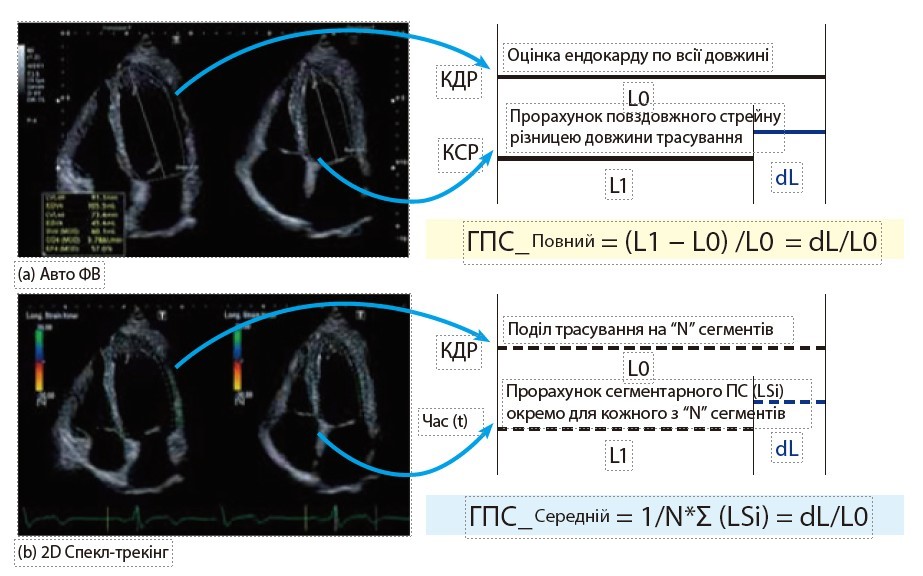

Пояснення розбіжностей у розрахунку глобального поздовжнього стрейну (ГПС) за допомогою Автоматичної ФВ та Спекл-трекінгу в апікальному 4-камерному зрізі6 КДР – кінцевий діастолічний розмір ЛШ, КСР – кінцевий систолічний розмір ЛШ

Результат розрахунку GLS, отриманий завдяки функції Авто ФВ розраховується співставленням різниць у довжині трасування ліній ендокарду в КДР та КСР [Рис. 3. (a)], із середнім GLS, розрахованим на основі значень GLS в апікальних 4- та 2-камерних зрізах6. В той час, як для 2D спекл-трекінгу GLS розраховується шляхом поділу лінії ендокарда на рівні довжини, а деформація розраховується на основі сумарних різниць довжини в кожній точці

[Рис. 3. (b)]6.